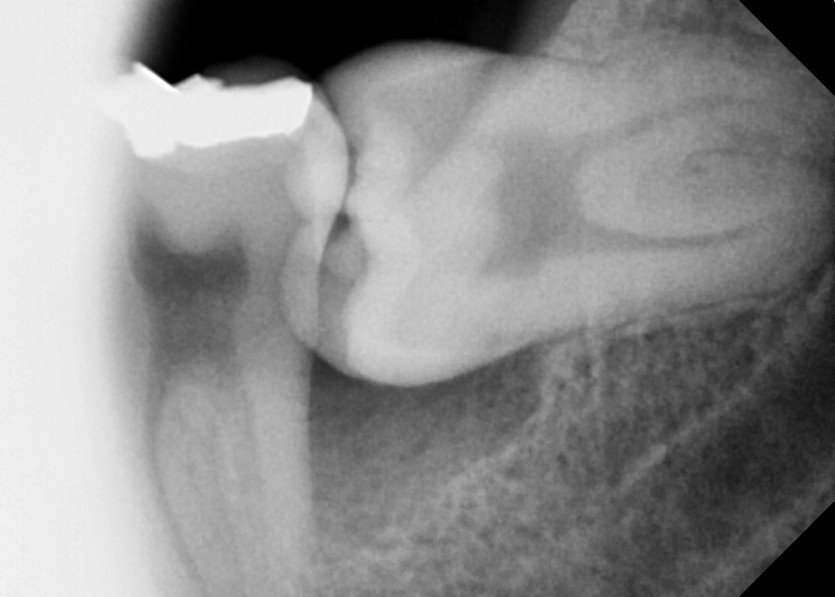

#28,38 사랑니 발치

구강외과 전문의가 당일 발치했습니다.